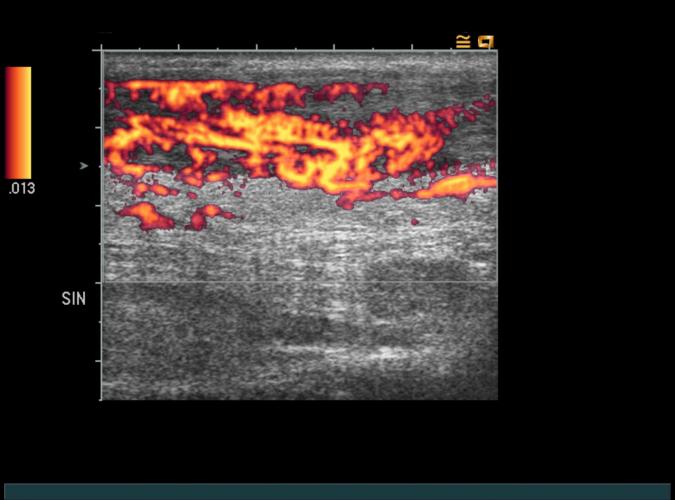

Samma patient som i 9p, kronisk tendinos/tendinit.

Long. vänster hälsena. Med power-Doppler påvisas hyperemi...patient går vidare till sklerosering. (9q)